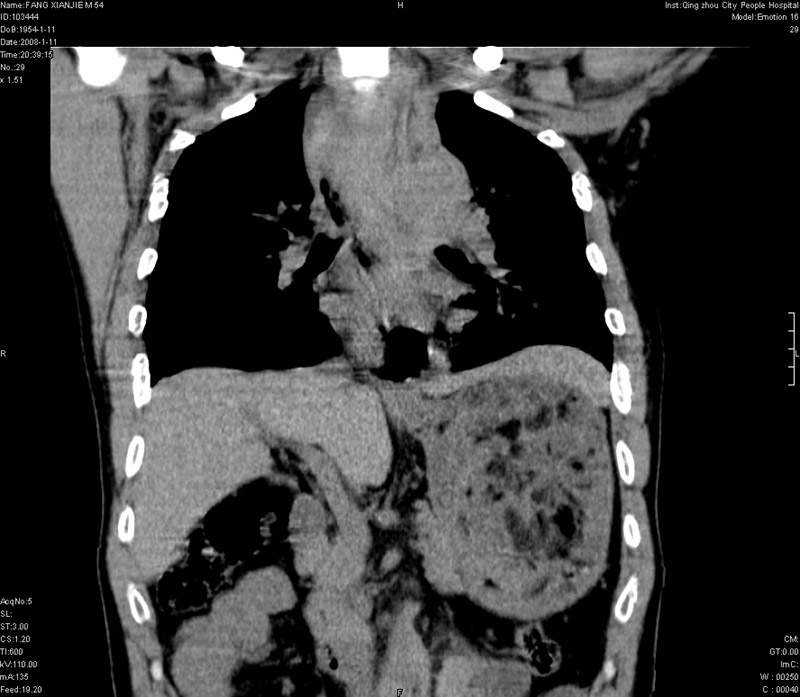

男性,40岁。胸部被车压伤伴胸痛1小时来院就诊。检查:一般情况尚可,血压110/80,胸部及上腹部压痛。结果在三天后公布。骨窗在横断位、冠矢状显示肋骨、胸椎、和胸骨未见骨折征象。

ct11308:胸部外伤1小时(证实病例) (2008-1-13 16:2)结果如下:病人入院后两小时后症状加重,8小时后在征得病人家属同意做了ct增强扫描。如下图。最终临床诊断:外伤性胸主动脉破裂并纵隔内血肿。由于有运动性伪影,胸骨在矢状面重建的图像似有骨折征,这是一种假象,我们称之为“假骨折”,这在多层ct重建中经常性遇到,必要时要结合横断图像鉴别之。现在,病人的一般情况较差,是否要手术家属尚有争议,如果手术修补,难度较大,需要专门预定制作固定支架。

以下是引用拾荒者在2008-1-16 18:46:00的发言:[br]ct11308:胸部外伤1小时(证实病例) (2008-1-13 16:2)结果如下:病人入院后两小时后症状加重,8小时后在征得病人家属同意做了ct增强扫描。如下图。最终临床诊断:外伤性胸主动脉破裂并纵隔内血肿。由于有运动性伪影,胸骨在矢状面重建的图像似有骨折征,这是一种假象,我们称之为“假骨折”,还有双侧肋骨的“假骨折”,这在多层ct重建中经常性遇到,必要时要结合横断图像鉴别之。现在,病人的一般情况较差,是否要手术家属尚有争议,如果手术修补,难度较大,需要专门预定制作固定支架。[br][br]再次表示感谢!

当然,对于该病例,其它非重要的诊断还有:右侧少量气胸;左侧胸腔积液;左侧轻度肺挫裂伤。对于纵隔内血肿,我们曾经遇到过多例,也有怀疑主动脉的破裂,但是,均未得到具体出血部位的明确诊断。